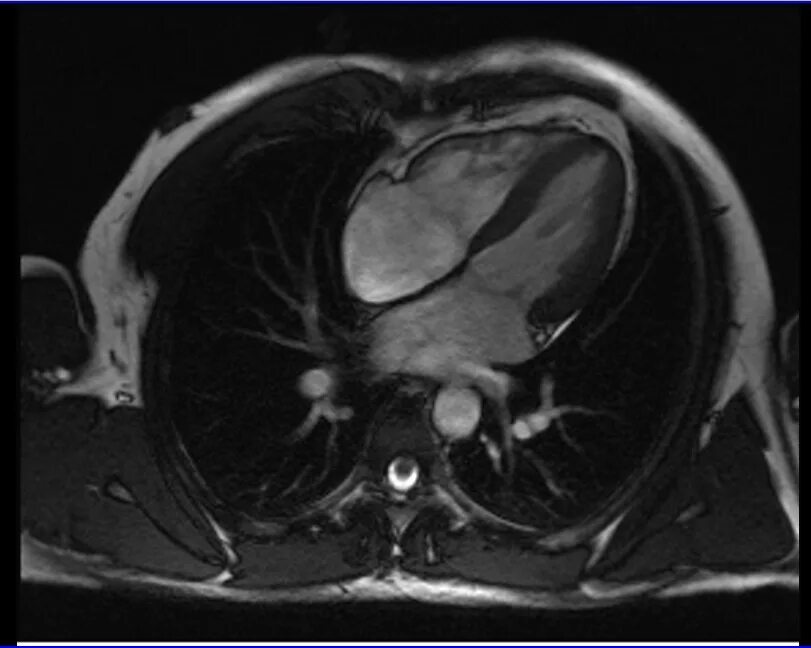

Как делают кт сердца